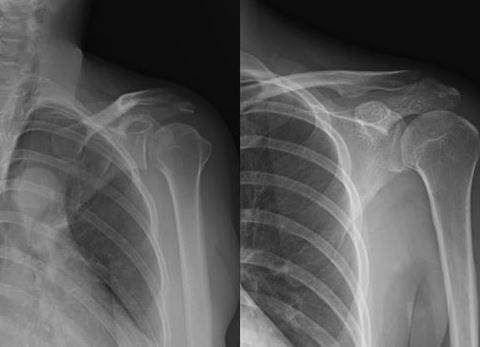

어깨충돌증후군치료법...